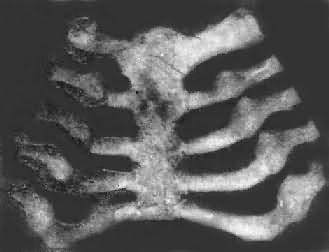

图17-11 佝偻病的肋骨 肋骨和肋软骨结合部呈结节状隆起,排列成行,形似串珠 除上述常见的佝偻病改变外,还有两种较少见的佝偻病,即①先天性或胎儿性佝偻病,在婴儿出生时已有佝偻病表现,主要是由于母亲在怀孕时有严重的维生素缺乏所致。②晚期佝偻病,多见于北方地区,发病多在10岁以后的儿童,故其改变介乎婴幼儿佝偻病和骨软化症之间。因此时颅骨的骨化已基本完成,而肋骨生长较慢,故方形颅和肋骨串珠等均不显著。骨骼生长较慢,严重时可形成侏儒畸形。 2.骨软化症病理变化骨软化症发生于成人,其改变与佝偻病相似。因成人的骨发育已停止,故其改变限于膜性化骨的钙化障碍,致过量的类骨组织堆积在骨的表面,骨质变软,同时因为承重力减弱而导致各种畸形,常见的有骨盆畸形,脊柱侧突及长骨弯曲等。骨盆畸形表现为骨盆的前后径及左右径均变短,耻骨联合处变尖而向前突出,呈鸟喙状,称为喙状骨盆。